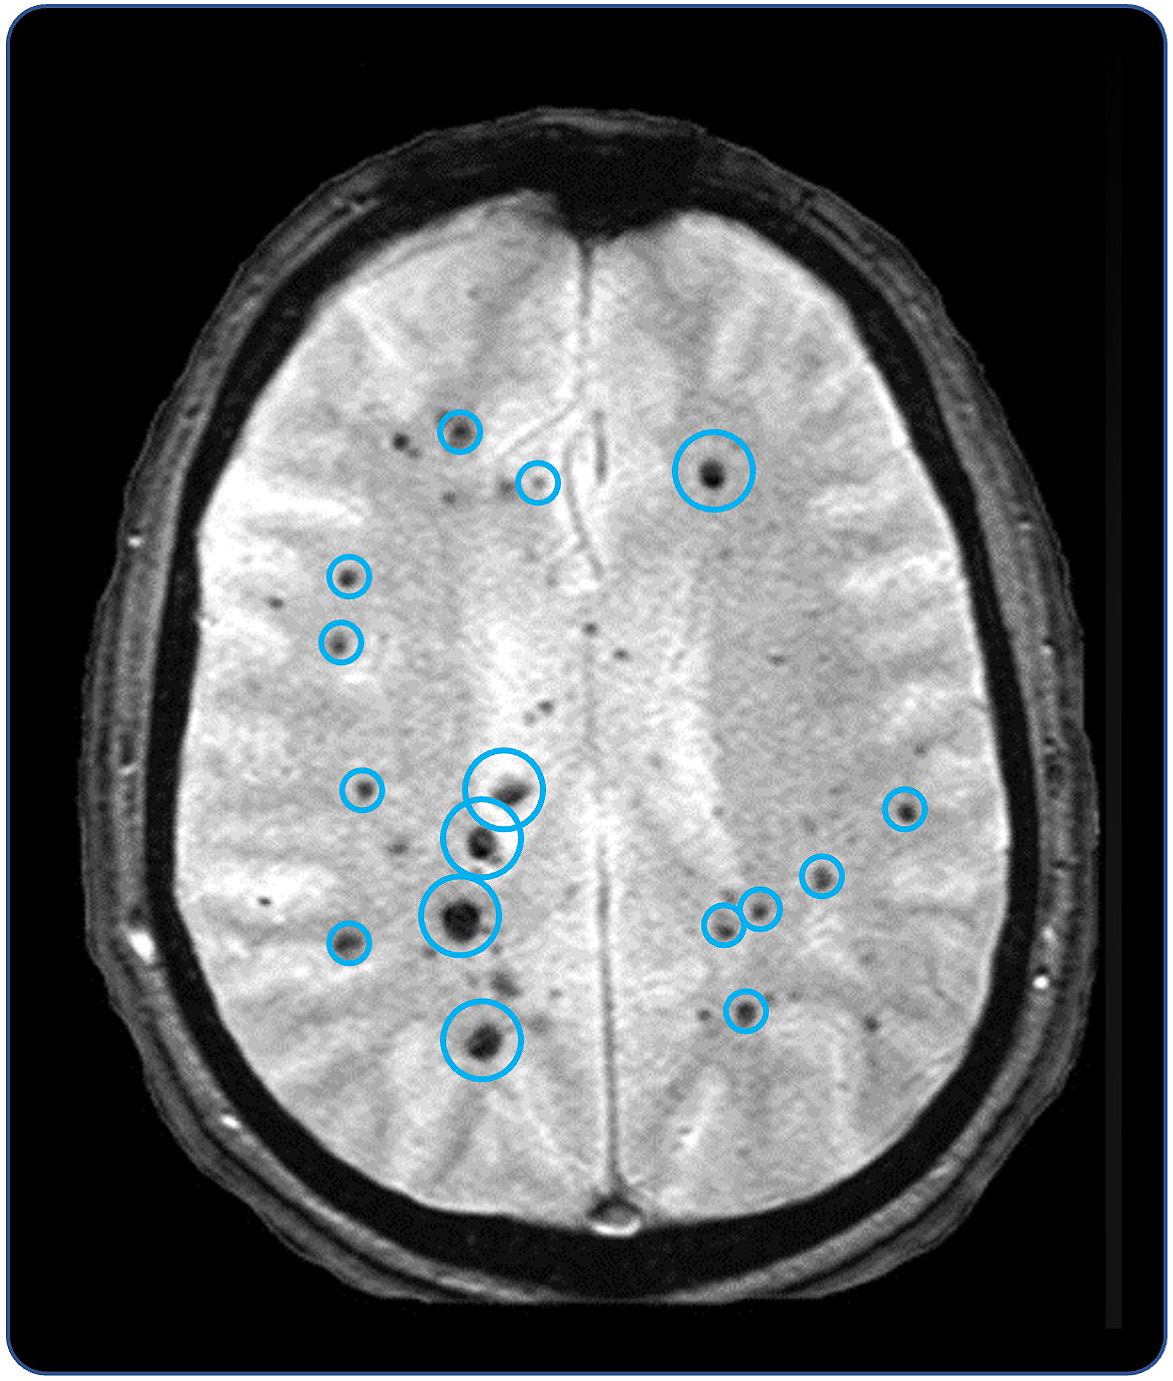

•Five phase 2 clinical-stage programs with multiple upcoming data readouts expected, including REC-994 in cerebral cavernous malformation (CCM) in Q3 2024, REC-2282 in neurofibromatosis type 2 (NF2) in Q4 2024, REC-4881 in familial adenomatous polyposis (FAP) in H1 2025, and REC-4881 in AXIN1 or APC mutant solid tumors in H1 2025

| | What’s more, the signs of AI-enabled point-solutions are already plentiful across our industry: •Protein folding •Scaled protein-ligand interaction prediction •Generative AI for chemistry for tractable targets •The FDA is already discussing the use of LLMs for program review •Major pharma companies are drafting regulatory filings like INDs by LLMs These facts lay out a clear future where efficiencies and improvements across the many current AI-enabled point-solutions will begin to combine into integrated ‘tech-stacks’ and workflows that will result in compounding improvements in our ability to drug historically undruggable targets, understand the underlying networks of biology with increasing fidelity, fast-follow newly validated biology, characterize disease in increasingly robust ways and ultimately deliver more, better medicines to patients to alleviate suffering at scale. The question is no longer whether this sort of future is before us, but when and who will lead it. Looking Back at 2023 and Before Reflecting back on late 2013 when Recursion was founded and how far we have come, it is simultaneously incredible and unsurprising to see where we are today. Recursion was then a Utah-based startup founded by two graduate students and a professor. Our first office was a conference room in the nearby University Research Park and our first laboratory was a converted storage room. Today, Recursion is a multinational, clinical-stage company leading the transition of BioTech into TechBio. We have over 500 employees, five clinical stage programs, one of the world’s largest biological and chemical datasets and two of the largest discovery collaborations in the industry with Roche/Genentech and Bayer. And in 2023, the opportunity ahead feels so much greater than it did in 2013, that in some ways it still feels like we are just getting started. In fact, from an internal perspective, 2023 felt like one of the best years in our history. In 2023 we achieved a lot of important milestones, and a lot of things we’ve been working to build, in some cases for years, really seemed to start hitting their stride, including: Pipeline •Five phase 2 clinical-stage programs with multiple upcoming data readouts expected, including REC-994 in cerebral cavernous malformation (CCM) in Q3 2024, REC-2282 in neurofibromatosis type 2 (NF2) in Q4 2024, REC-4881 in familial adenomatous polyposis (FAP) in H1 2025, and REC-4881 in AXIN1 or APC mutant solid tumors in H1 2025 •Completed a Phase 1 study for REC-3964 in healthy volunteers for the potential treatment of Clostridioides difficile (C. difficile) infection with a favorable safety and tolerability profile •Advanced our RBM39 program in homologous recombination proficient ovarian cancer and other solid tumors to IND-enabling studies •In-licensed a program (Target Epsilon) that emerged from our fibrosis collaboration with Bayer that represents a novel approach to treating fibrotic diseases with compelling early data |